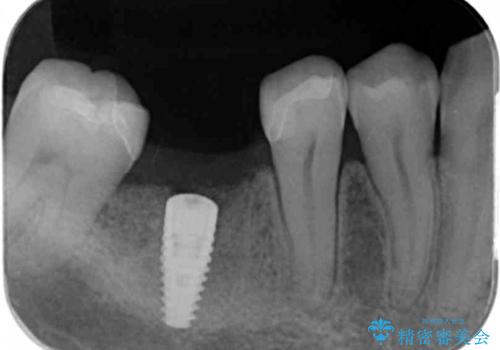

- 歯の破折により失ってしまった右下の歯の機能回復を求めて来院されました。

取り外しの必要な入れ歯や、歯を大きく削る必要のあるブリッジではなく、インプラント治療を希望されました。

骨の増成を含むインプラント治療を計画します。

安定し、長く使用できるようなインプラント治療を実践するため、骨の増成をインプラント埋入と同時に行いました。